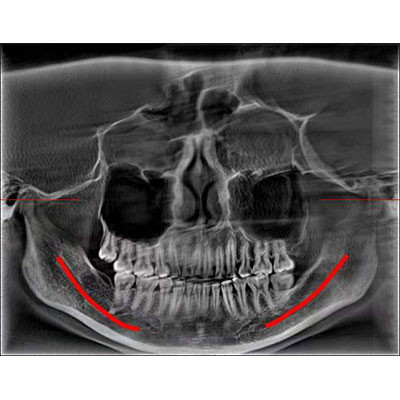

通過三維容積影像,提取高清口腔全景影像。

專有圖像校正技術(shù),去除金屬偽影,提高圖像分辨率。